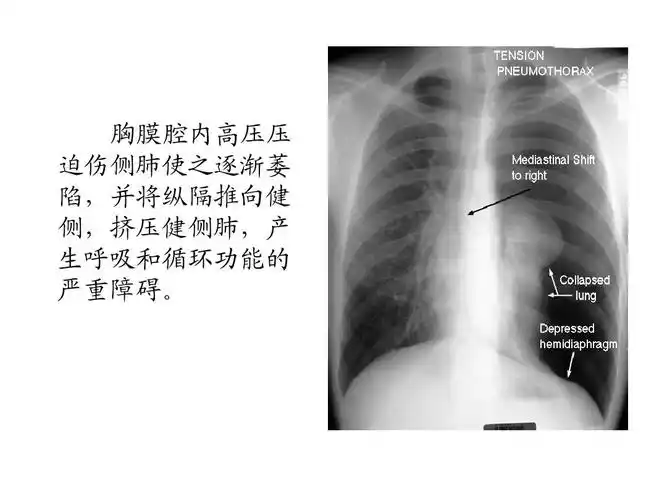

张力性气胸ppt